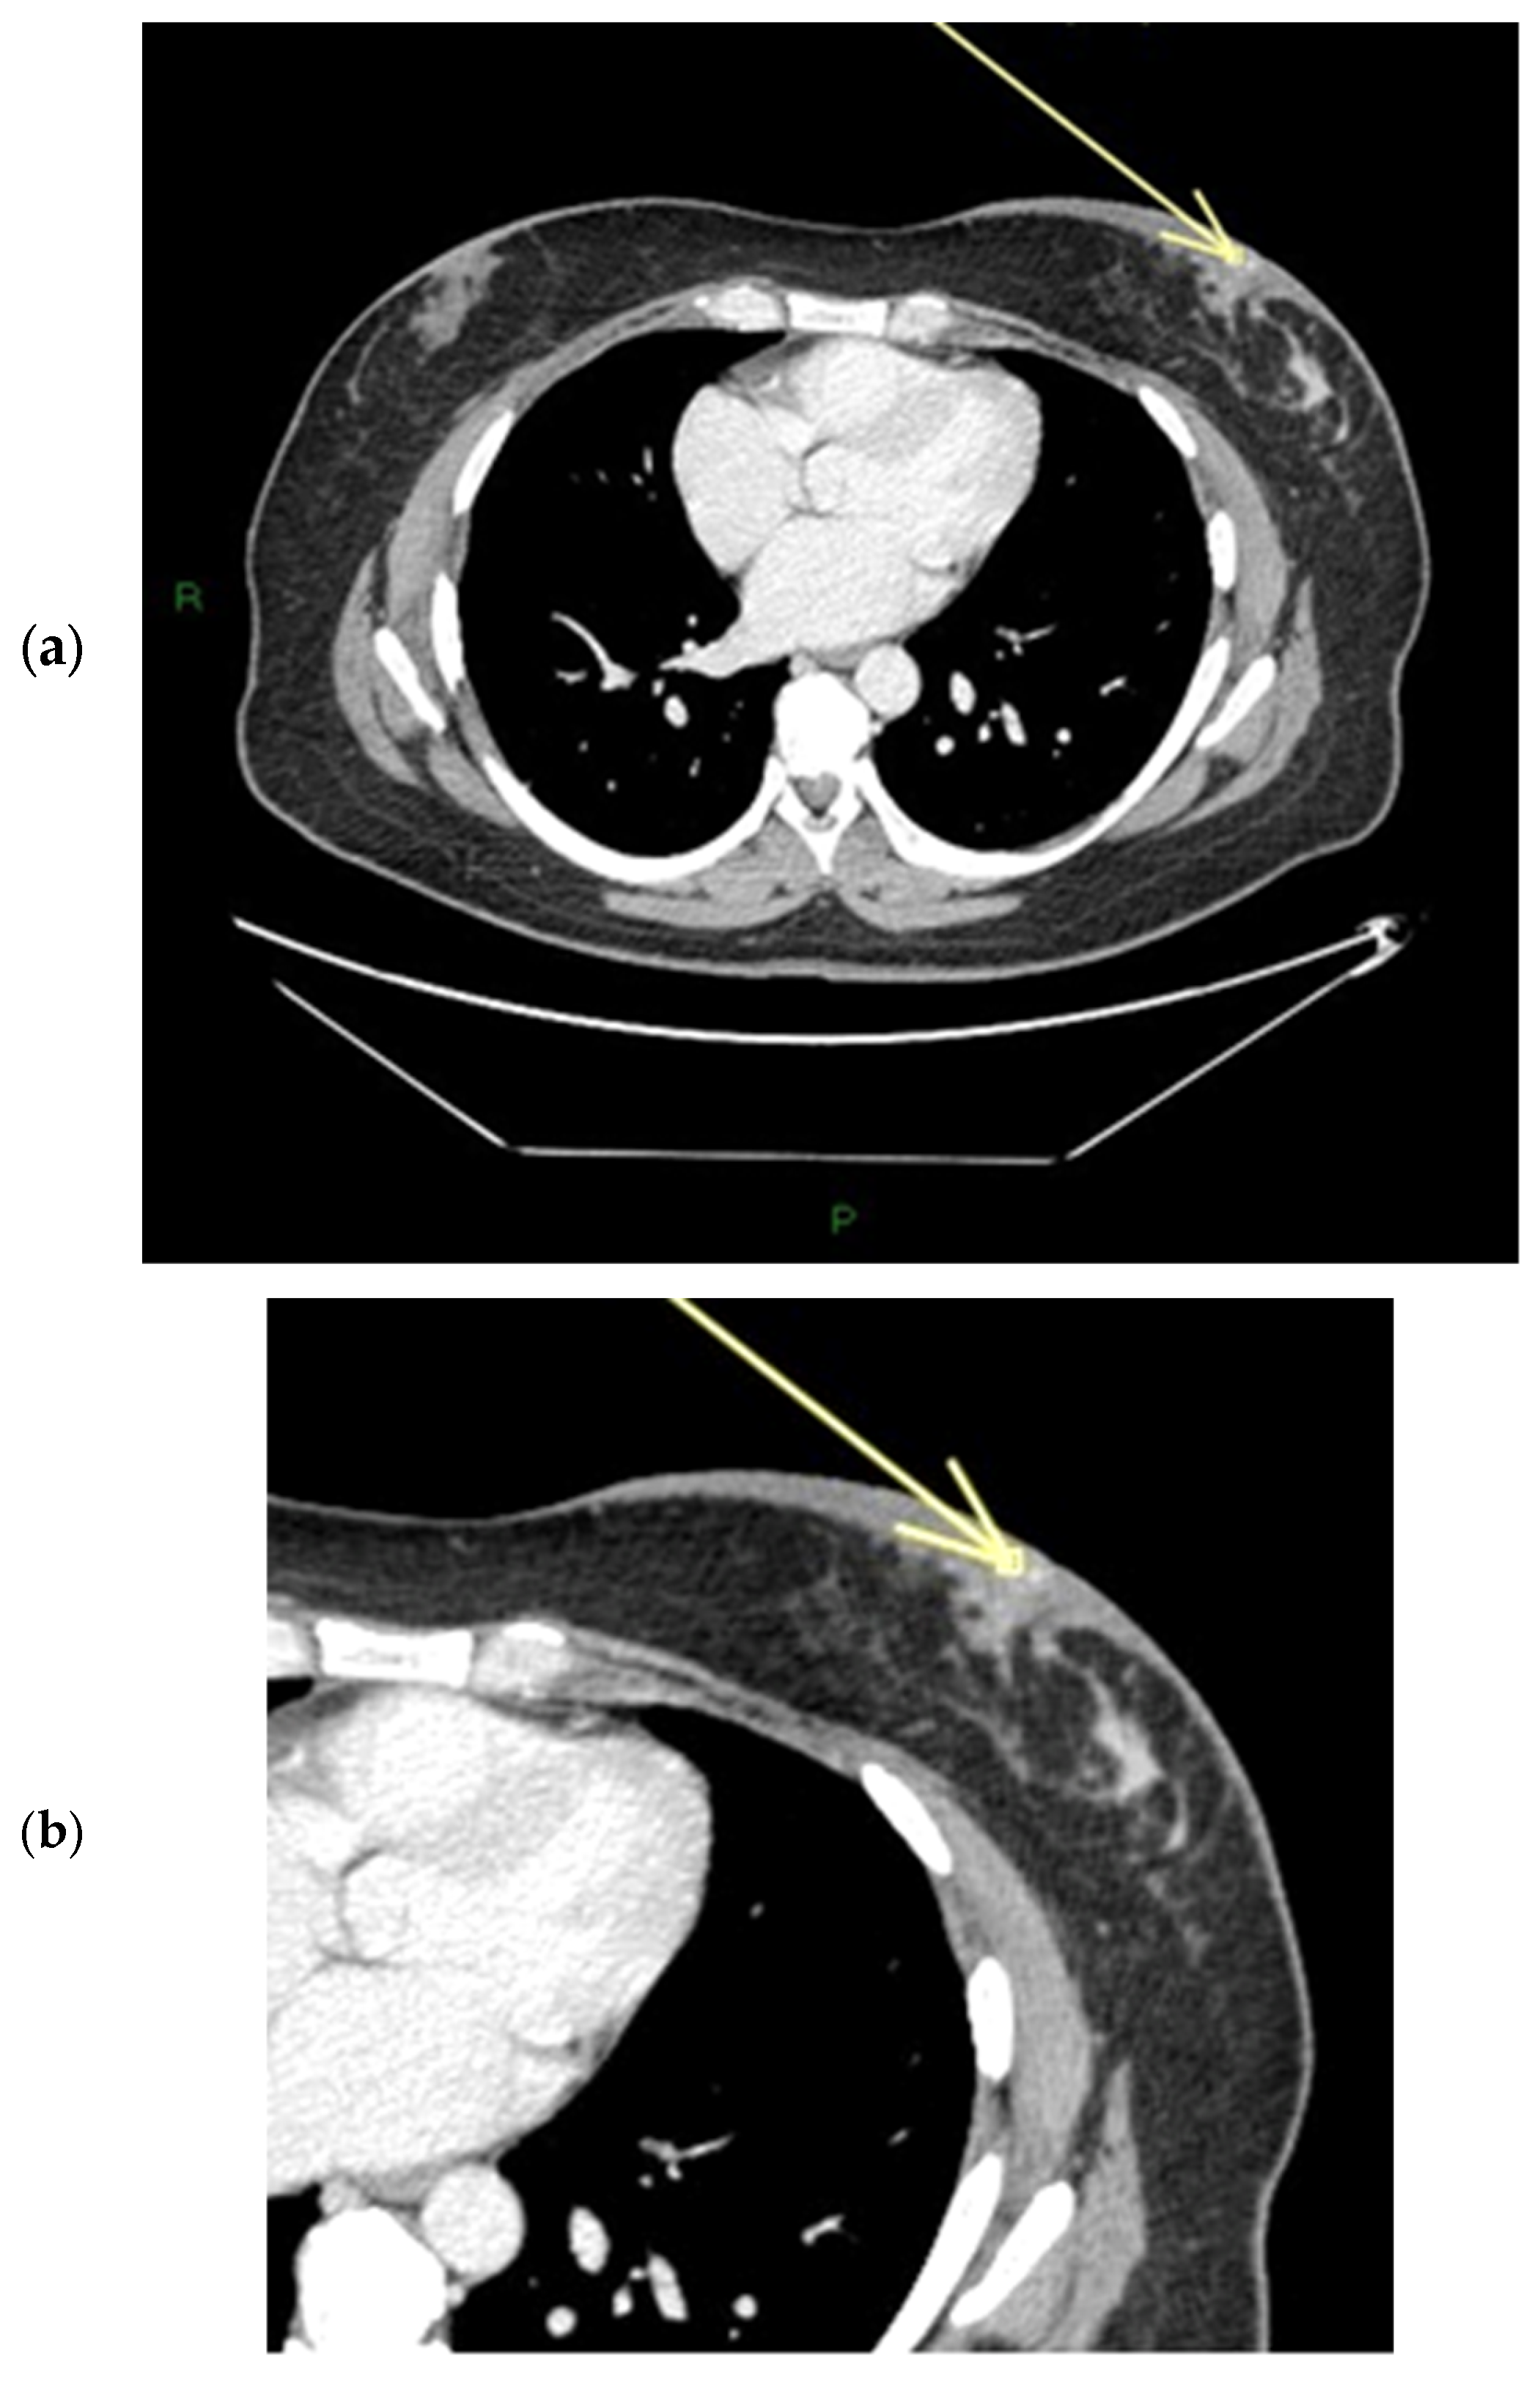

Figure 4.

(a,b) Patient’s name R.M. In the MIP (maximum-intensity projection) reconstruction of the first post-contrast fat-suppressed T1 sequence, we can observe a gross area of pathological enhancement, which affects the external quadrants of the left breast and infiltrates the nipple (a). During ce-MR, no SLE and no NEZ are present in the affected left breast nipple; the arrow indicates marked patchy nodular INE of the left breast nipple (b).

Figure 5.

(a,b) Patient’s name R.M. In the ce-CT scan, the arrow shows enhancement of the base of the left nipple alone (and not of the body).

Figure 6.

Patient’s name R.M. During PET/CT, the pathological NAC-SUV value is measured at the base of the left nipple.